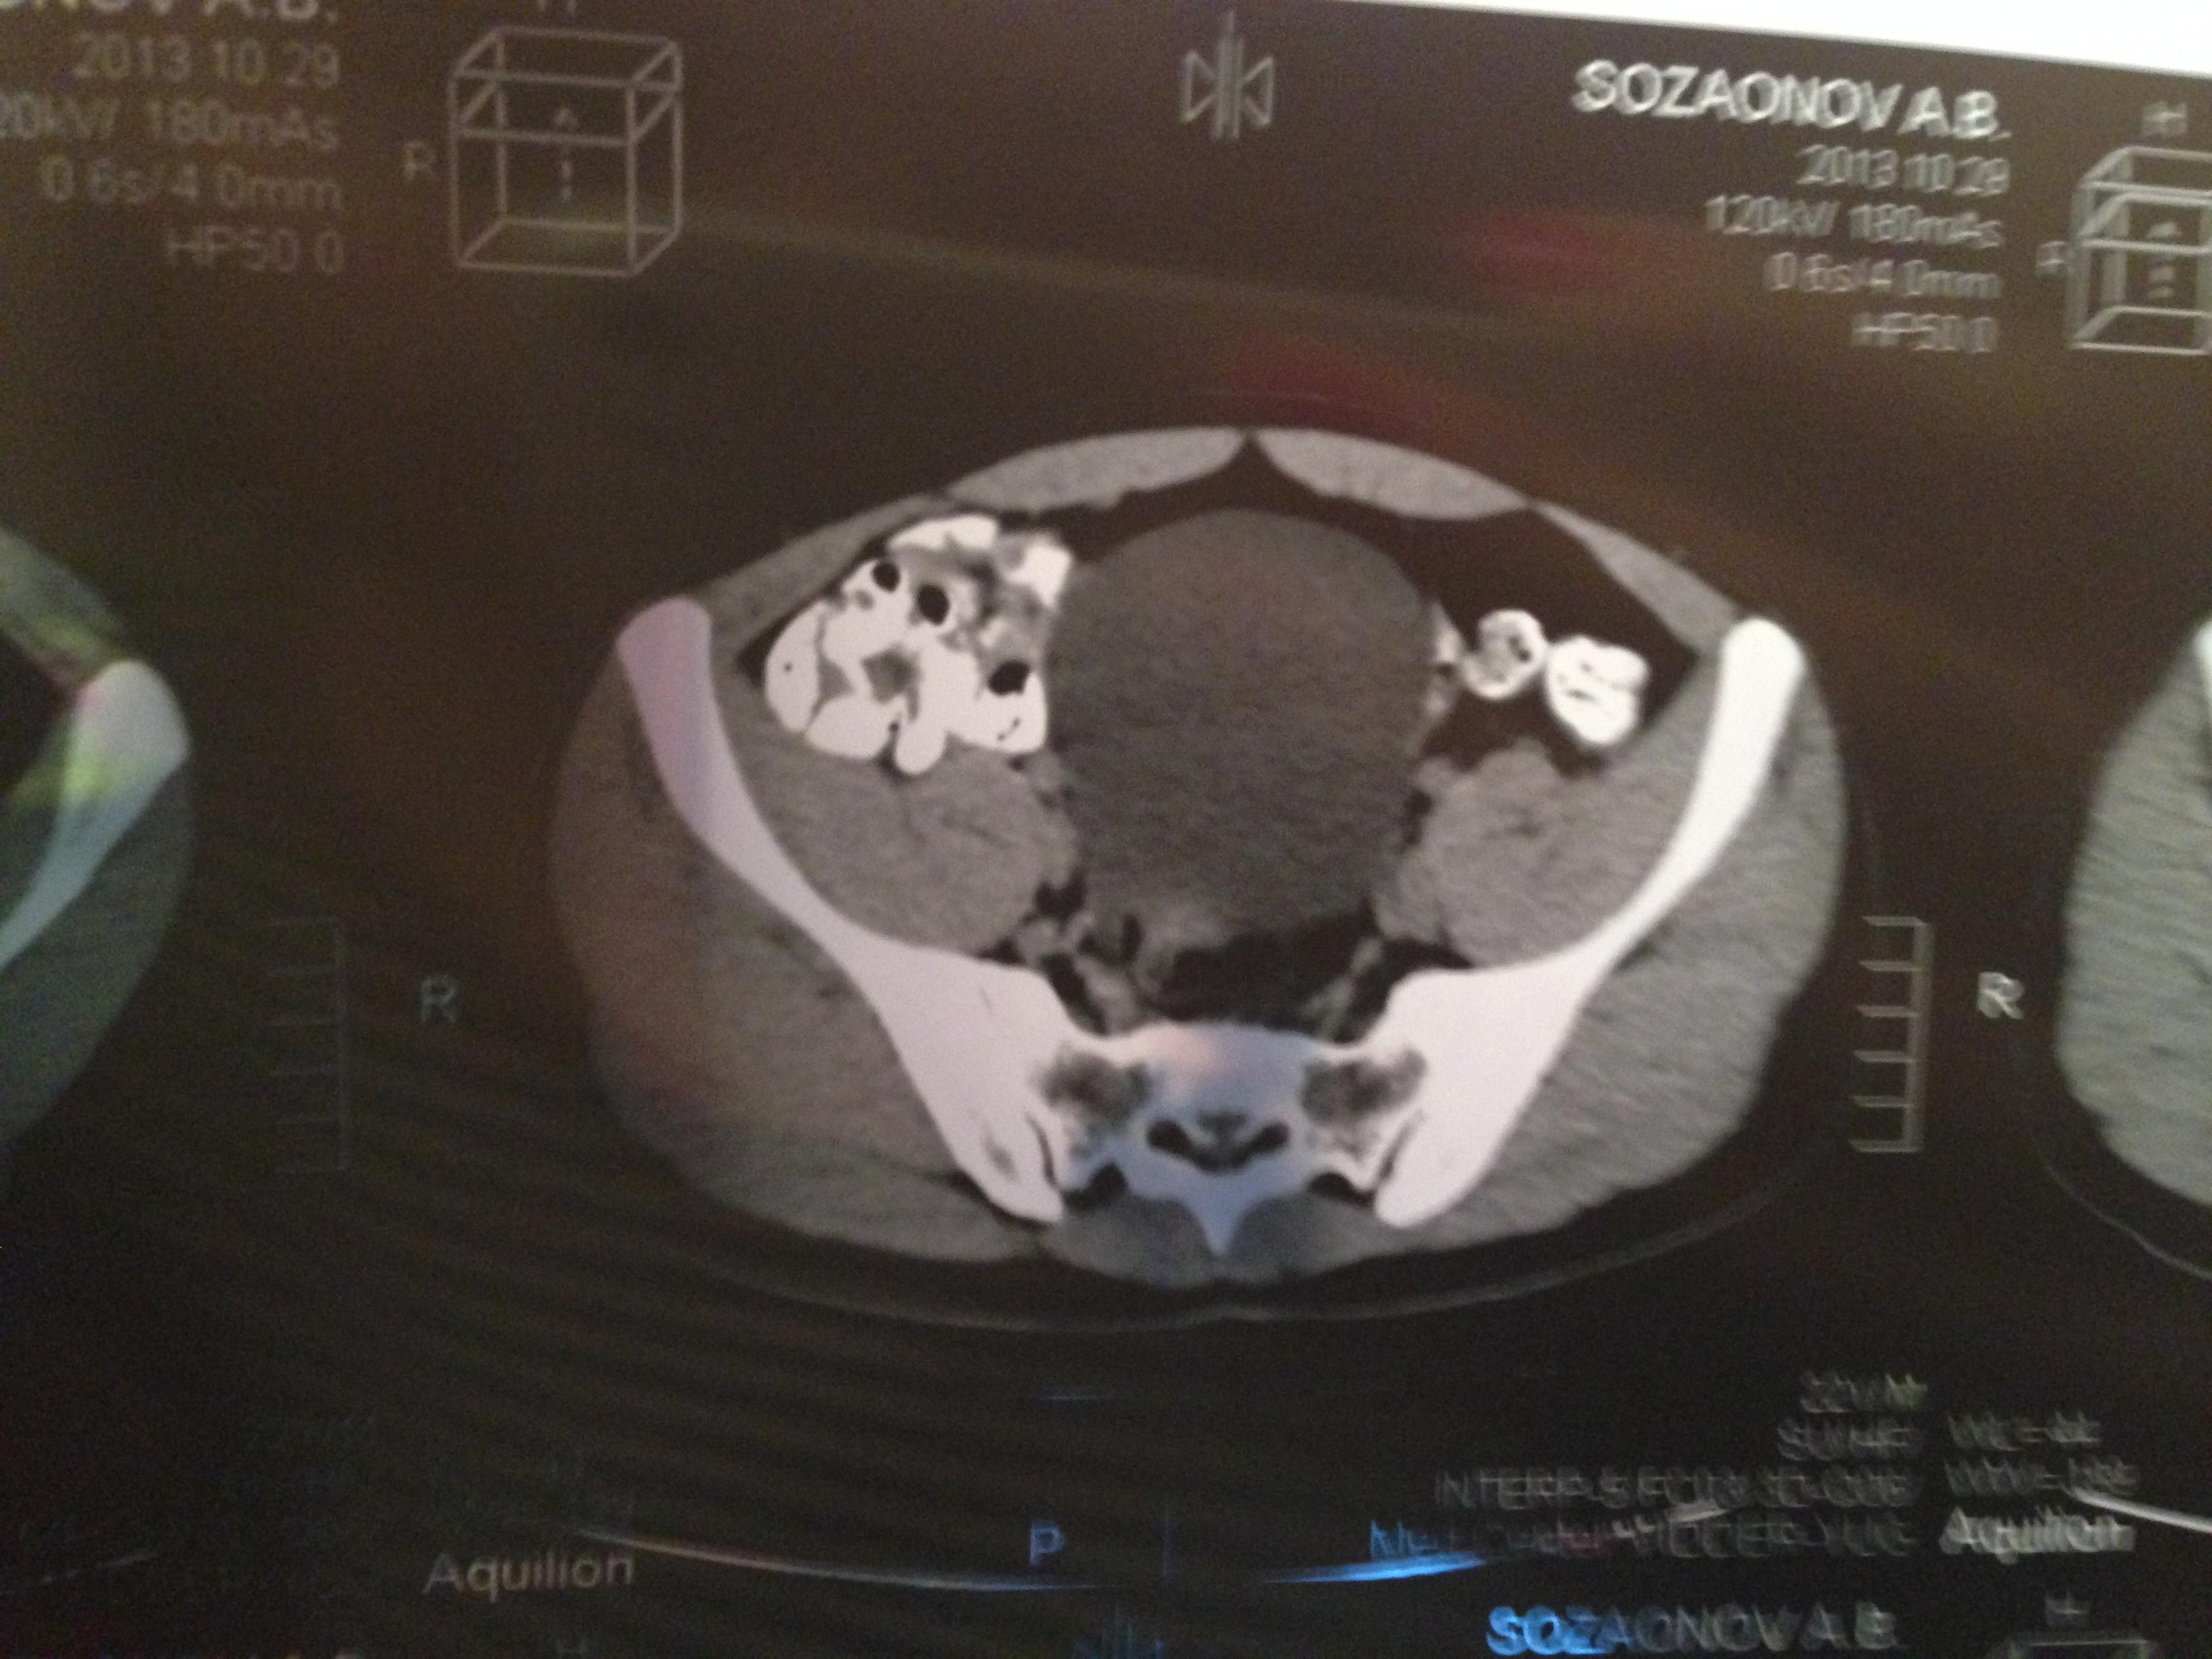

проведена МСКТ области таза!Внеорганных дополнительных патологических образований,лимфаденопатии или свободной жидкости в области таза не выявлено.

Мочевой пузырь-наполнен,стенки не утолщенны,паравезикально-без грубой органки.

Граница между предстательной железой и пузырем несколько четкая,контур пузыря на данном уровне не деформирован.

Предстательная железа-без грубой органики,еденичные микрокальцинаты.

Семенные пузырьки-конфигурация не совсем типична,примерный размер правого 26*28мм.Отмечаются признаки кистовидной трансформации и микрокальцинации обоих пузырьков.Наибольшая из кист слева достигает 9 мм.Обращает на себя внимание неравномерная кальцинация стенок крупных регионарных(текстикулярных)артерий с обоих сторон.

Заключение:на момент исследования,КТ-данных за наличие внеорганных дополнительных патологических образований,лимфоденопатии или свободной жидкости в области таза не выявлено.КТ-признаки в пользу проявлений калькулезного везикулита с элементами кистовидной трансформации семенных пузырьков.